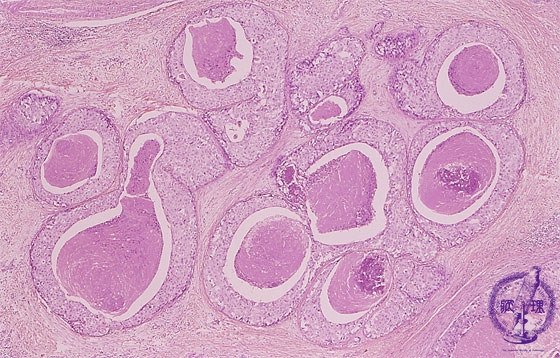

- ★(5)noninvasive carcinoma (comedo type)

Microscopic image(HE stain, low power view):Intraductal spreading carcinoma demonstrating comedo-like central necrosis within cell nests. Sometimes necrosis accompanied by calcification (arrow head).